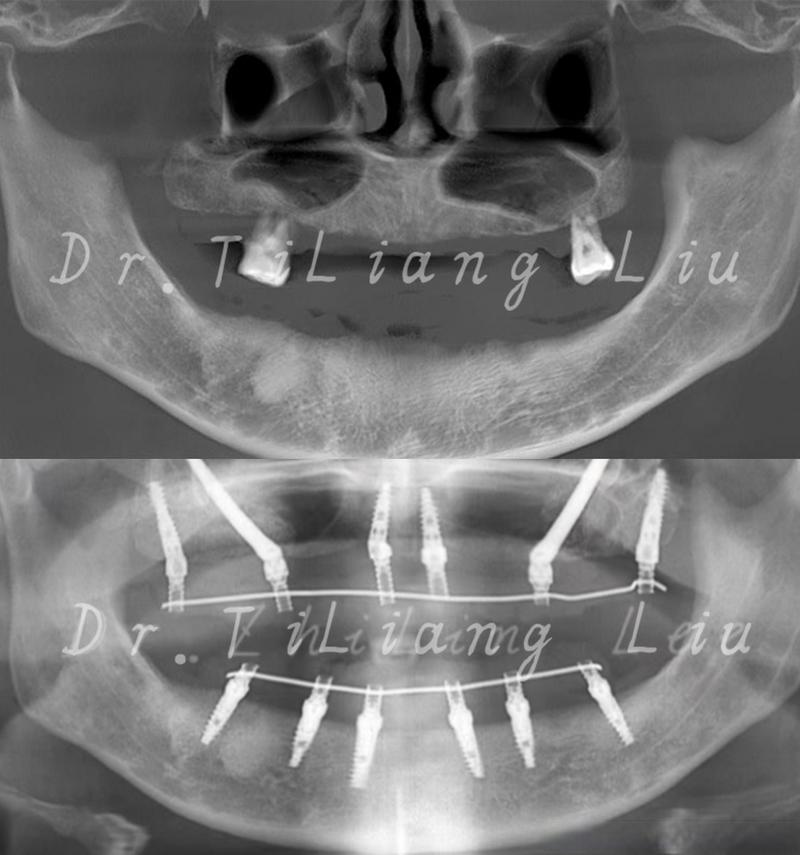

上颌种植8颗通常采用“All-on-8”技术,通过前牙区与后牙区种植体的合理分布,兼顾美学与力学支撑,种植体位置需避开上颌窦、颏孔等重要解剖结构,同时确保咬合力均匀分散。

种植体位置分布(以全口无牙颌为例)

| 前牙区(中切牙、侧切牙) | 4颗(每侧2颗) | 承担美学功能(维持前牙区丰满度)及部分咬合力,种植体角度较直,利于前牙区牙冠排列。 | 直径3.5-4.5mm,长度10-12mm |

| 后牙区(第一前磨牙至第二磨牙) | 4颗(每侧2颗) | 承担主要咀嚼功能,种植体可 slightly 远中倾斜(15°-30°),避开上颌窦,同时分散咬合力。 | 直径4.0-5.0mm,长度8-12mm(需结合骨量调整) |

通过CBCT(锥形束CT)三维扫描,明确牙槽骨的骨量(高度、宽度)、密度,以及上颌窦底位置、下牙槽神经管等解剖结构,若骨量不足(如上颌窦气化导致骨高度不够,或牙槽骨宽度<5mm),需先进行骨增量治疗,如上颌窦内/外提升术、骨块移植、引导骨再生术(GBR)等,为种植体提供充足骨支持。